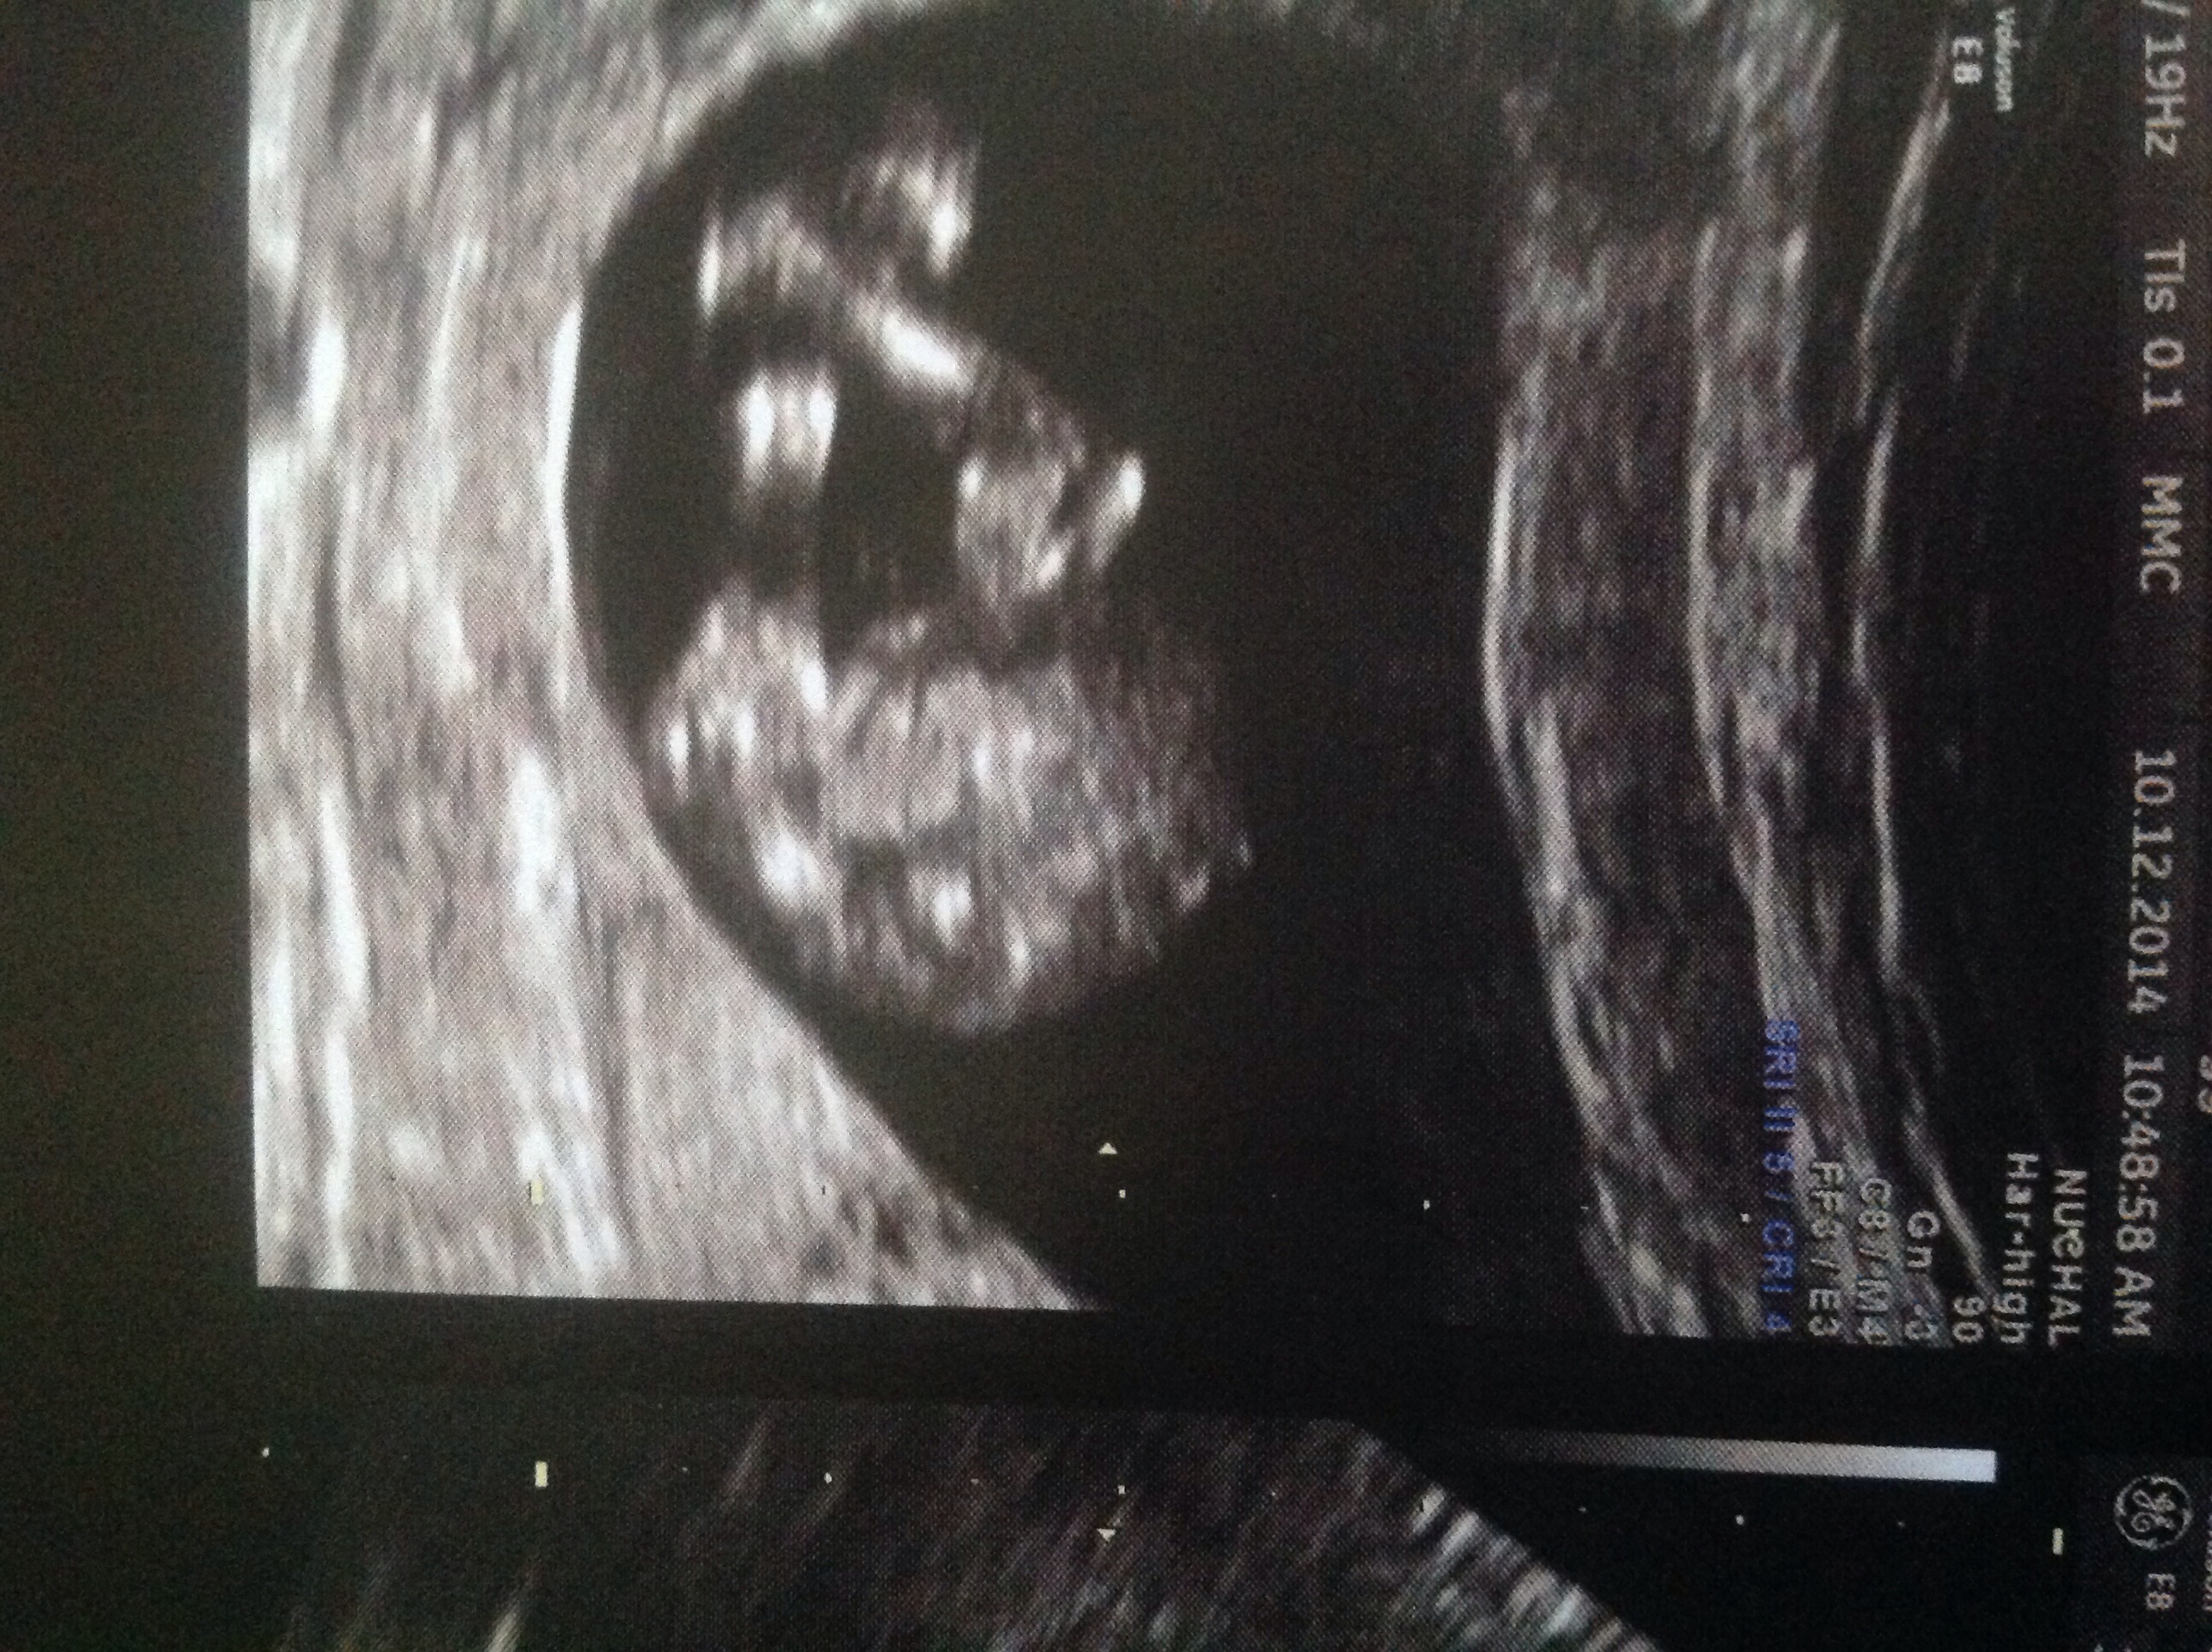

12 weeks 4 days

I know potty shots at this gestation are not that reliable,but just putting this up for a bit of fun to pass the time. I don't have a pic of the nub unfortunately.Attachment 22557Attachment 22557

Looks like a little girl.

Looks girly

Found out yesterday at 17+1 that she is indeed a girl! So very happy and excited! Thank you to everyone that took the time to guess :bigsmile: